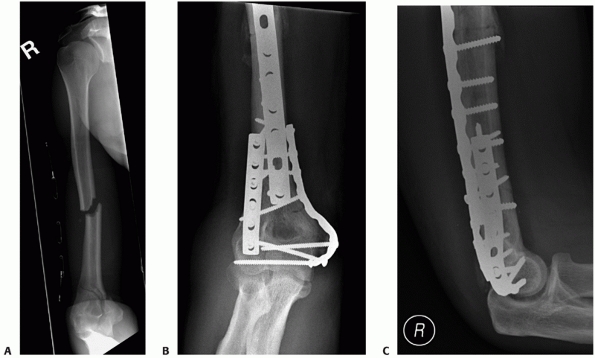

![]() |

FIGURE 33-22

A 21-year-old man sustained an intra-articular distal humerus fracture associated with a coronal shear fracture of the capitellum (A,B). The capitellar fracture was fixated with a minifragment plate applied posteriorly and a headless compression screw. The articular segment was then rigidly linked to the humeral shaft with a parallel plating technique (C,D). (C, capitellum.) |